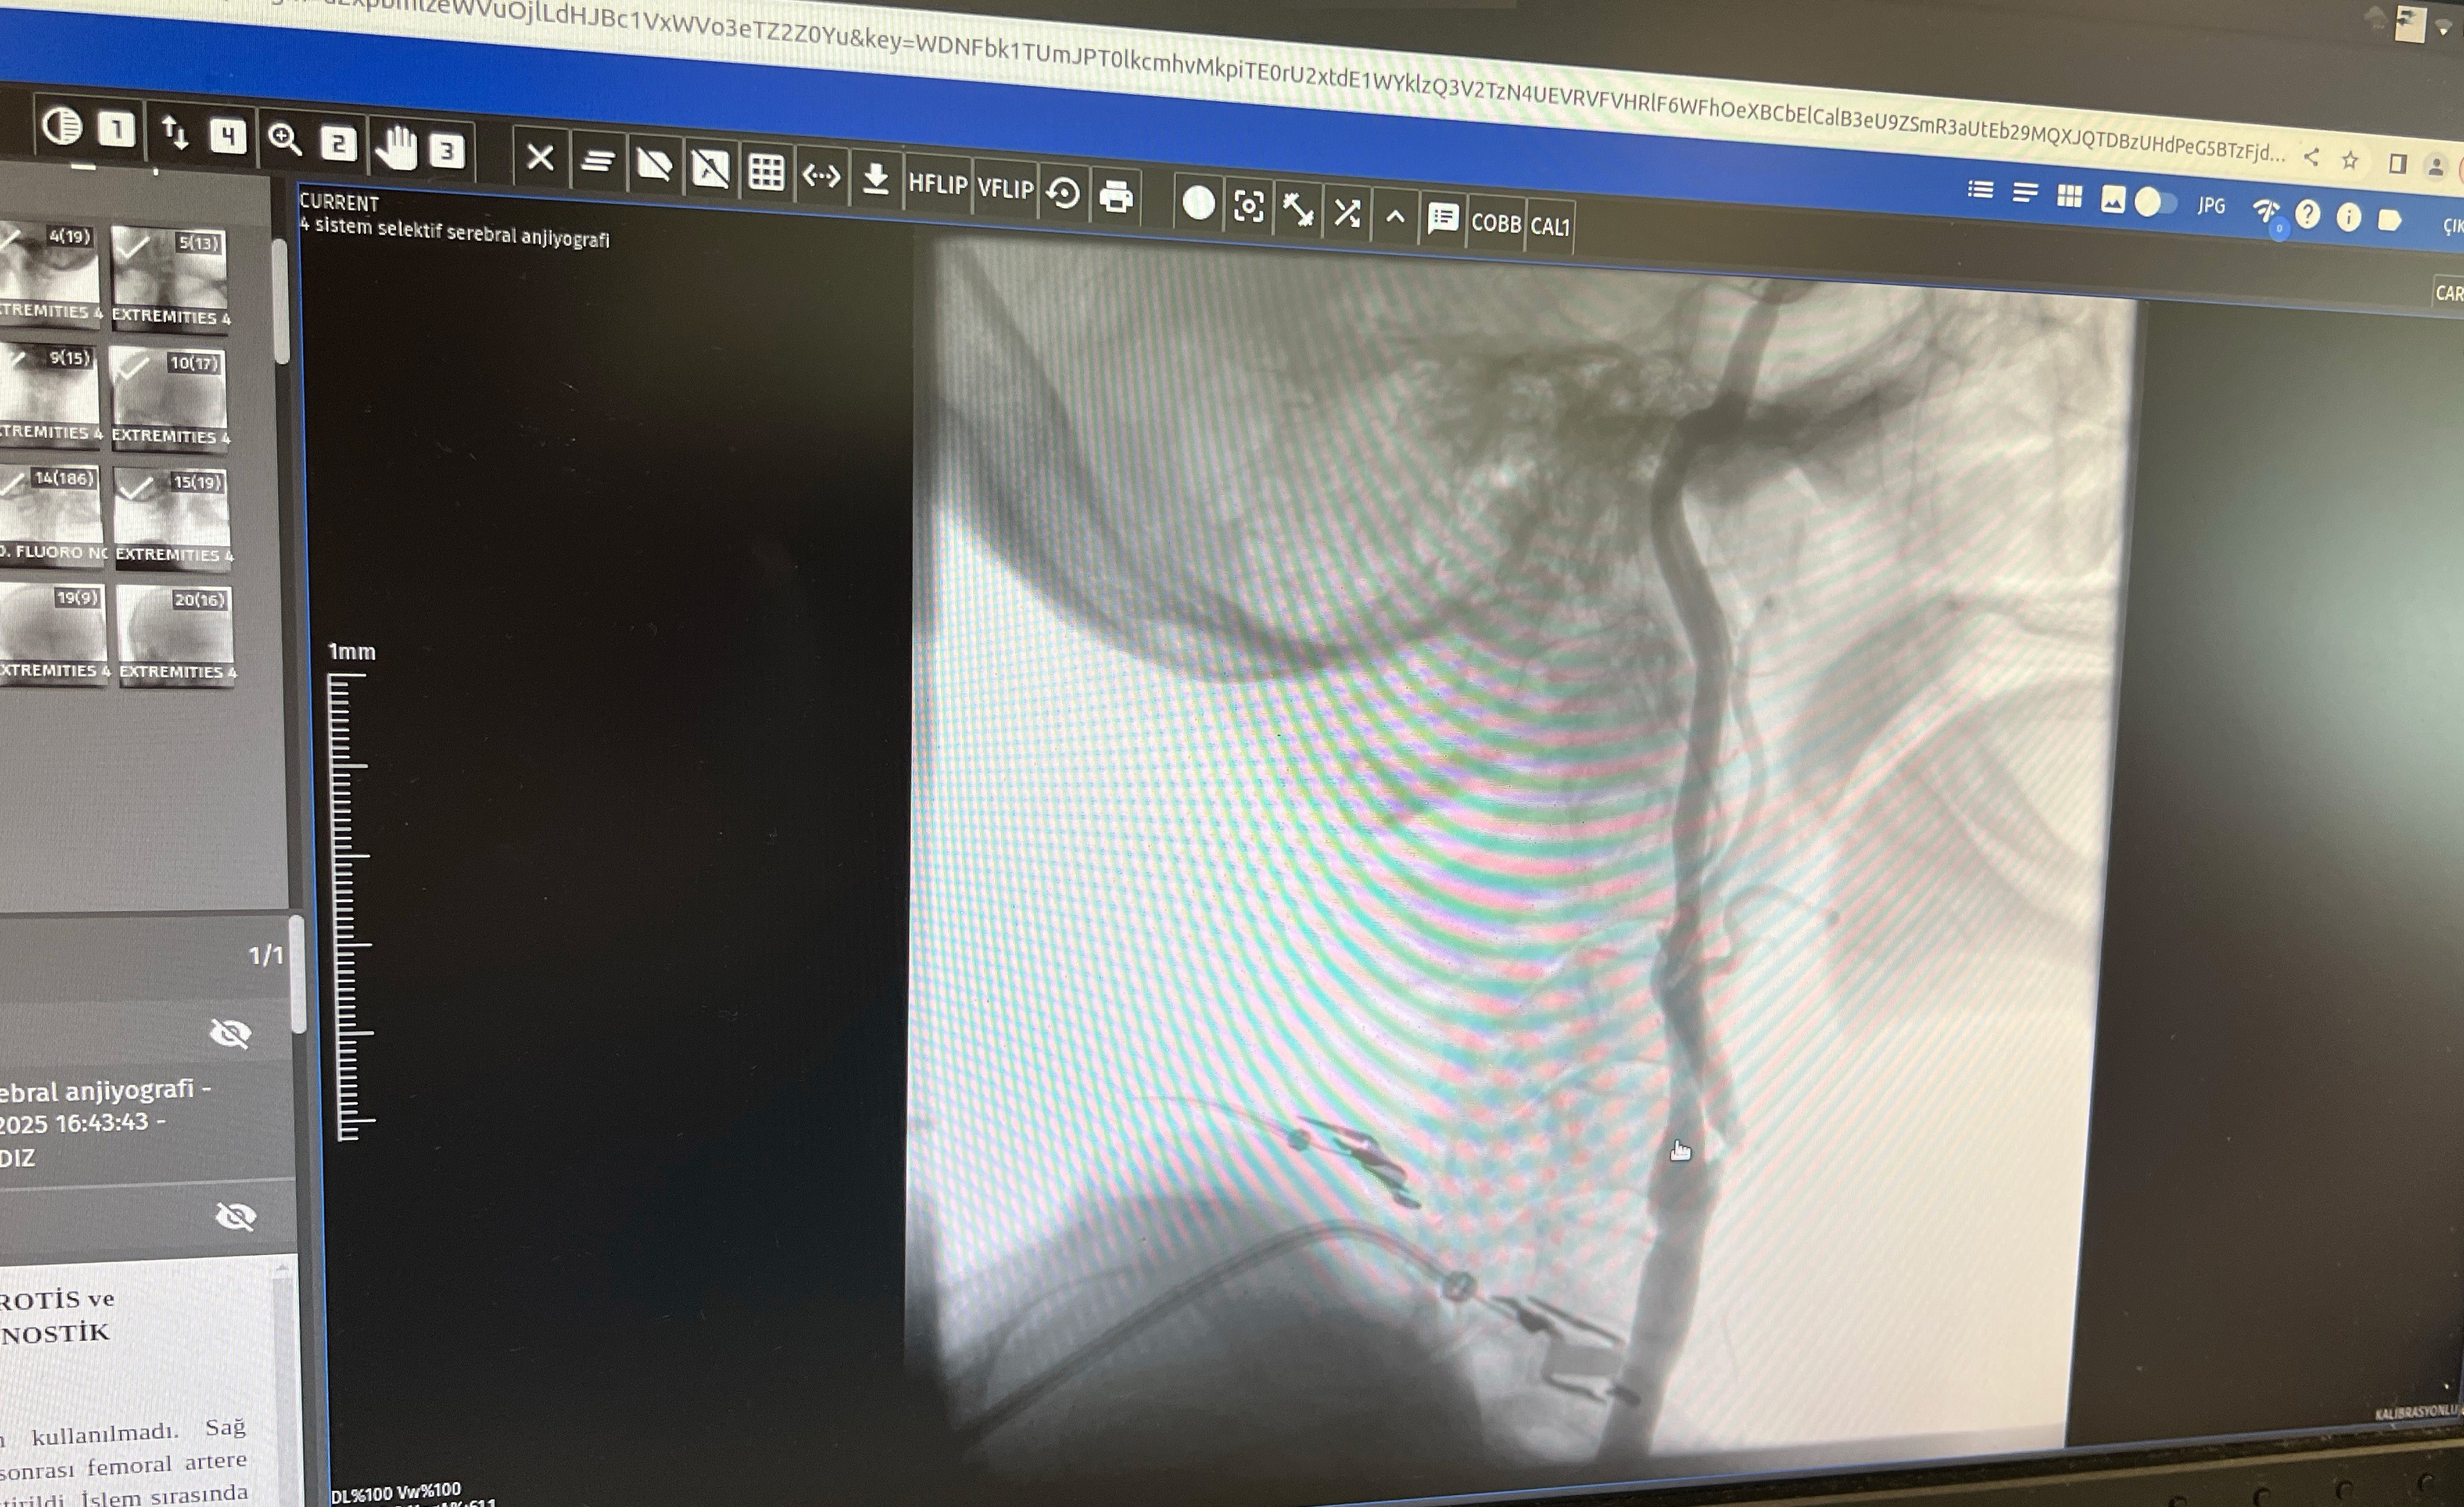

"Boyun damarlarını açma işlemi iki şekilde yapılabilir. Bir karotis endarterektomi dediğimiz ameliyatla bir diğer yöntem ise perkutan girişim dediğimiz stent yöntemiyle açılabilir. Biz kliniğimizde nöroloji ve kardiyoloji olarak bir konsey yapıyoruz. Damarı ciddi tıkalı olan ve buna bağlı felç geçirmiş hastalarda bu konseyde hastaya işlem yapıp yapmama kararı veriyoruz. Verdiğimiz karar çerçevesinde eğer hastaya işlem kararı vermişsek femoral arter dediğimiz kasık arterinden bir şitle 6 ya da 7 F çapında bir şitle ince bir boruyla bu damara giriş yapıyoruz ve boyun damarlarına ulaşıyoruz. Özellikle teller, filtreler ve stentlerle bu damarları açıp hastanın tedavisini gerçekleştiriyoruz. İşlem ameliyatsız olduğu için hastamız ertesi gün rahat bir şekilde problem olmazsa işlemde taburcu olabiliyor bu işlemden sonra.

Bu işlemin yapılması için özellikle anjiografinin olduğu girişimsel nöroloji uzmanının ve girişimsel kardiyoloji uzmanının olduğu ve bu konuda yeterli vaka tecrübesine ve deneyime sahip uzmanların olduğu merkezler gerekir. Bunu yapabilmek için belli bir vaka sayısına ulaşmak ve bu konuda tecrübeli olmak gerekiyor. Biz de Manisa Şehir Hastanesi'ndeki girişimsel kardiyoloji ve nöroloji uzmanları olarak bu işlemi kliniğimizde efektif bir şekilde gerçekleştiriyoruz."